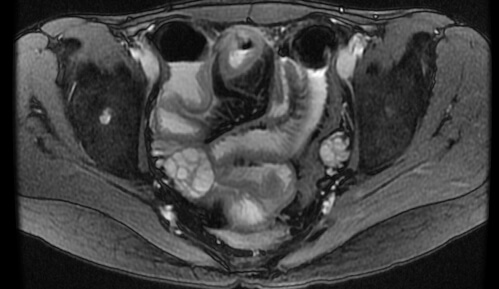

MR enterography is valuable for determining extent of inflamed bowel, discriminating between active inflammation and chronic fibrosing disease, detecting fistulae, and detecting strictures. Additionally, MRI can provide excellent delineation of the course of perianal fistulas, including relationships to sphincters and levators.

Before undergoing MRI to evaluate the bowel, one drinks a little over one quart of a fluid that helps to distend the bowel, and an intravenous catheter is placed so that intravenous contrast can be administered.